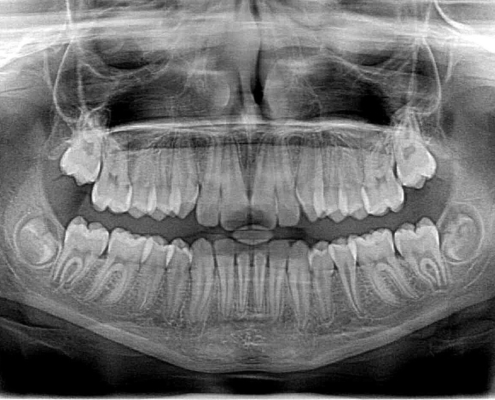

Wurde die bisher meist anhand von einfachen, 2-dimensionalen Röntgenbildern gemacht, kombiniert mit im Labor angefertigten Modellen, so greifen wir bei uns in der Praxis auf die 3D-Diagnostik zurück.

Wir verfügen bei uns in der Praxis über ein sogenanntes DVT (dentale Volumentomographie).

Dies funktioniert ähnlich wie ein CT: Es erstellt ein dreidimensionales Bild des Kiefers, welches in einzelnen Schnitten betrachtet werden kann.

So kann man schon im Vorfeld Implantate am Computer virtuell in den Kiefer setzen, kann genau sehen, wo genug Knochen vorhanden ist und wo gegebenenfalls noch ein Knochenaufbau nötig ist.